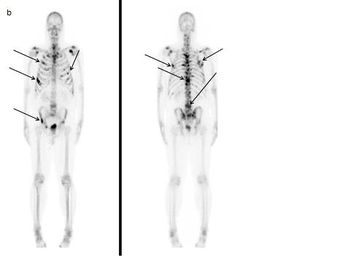

Nuclear medicine uses radioactive substances, called radiopharmaceuticals, in the diagnosis and treatment of a range of diseases. These substances are chosen or especially developed to be taken up predominantly by one organ or one type of cell in the body. Nuclear medicine offers unique diagnostic information in oncology, cardiology, endocrinology, neurology, nephrology, urology and other areas. Such information is not obtainable, or obtainable only with less accuracy, by other modalities. For nuclear medicine diagnostic procedures, trace amounts of radiopharmaceuticals are administered to patients through injection into veins (intravenous), skin (intradermal) or tissues (intraparenchymal) as well as breathing in (inhalation) or eating/drinking (ingestion). After intake, the function, or physiology, of various tissues, organs or organ systems can be demonstrated. For example, in cancer patients, nuclear medicine imaging can be used for diagnosis (i.e. is a cancer present), staging (i.e. how far has it spread), assessment of response to therapy or of possible disease recurrence. Nuclear medicine cameras are now commonly combined with a CT unit (e.g. hybrid SPECT/CT and PET/CT) which allows precise anatomic localisation of pathology. (Figure 1, Figure 2a, 2b)

Nuclear medicine procedures for treatment are non-invasive and present no risk of direct complications to patients, but limited to several well-established situations where killing hyperfunctioning or malignant cells is important (for example hyperthyroidism, cancer of the thyroid, degenerative and inflammatory diseases of joints, palliative treatment of metastases to the skeleton). In addition, there are many studies showing significant potential for radio-labelled antibodies and receptor-avid peptides to be used in the treatment of several malignancies.